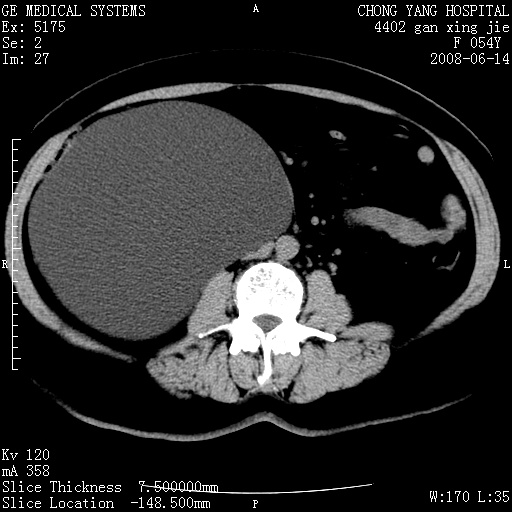

标题: CT14033:F54Y,来源哪? 外伤发现,自述既往无不适。 [打印本页]

标题: CT14033:F54Y,来源哪? 外伤发现,自述既往无不适。

1、脂肪肝。2、腹腔囊性占位,首考虑来源于右肾下极,其次考虑来源于肠系膜。

考虑肠系膜囊肿,脂肪肝

肠囊肿可能性大,与十二直肠水平部呈喇叭口,来源于十二直肠,不排除胰头假囊肿.

1、脂肪肝。2、腹腔囊性占位,首考虑肠源性囊肿或中肾管囊肿。

脂肪肝,来源于腹膜后囊肿可能性大。

脂肪肝,巨大肾囊肿

支持考虑肠系膜囊肿,脂肪肝.

考虑肠系膜囊肿

1)脂肪肝。2)右肾下极巨大囊肿。

右肾下极巨大囊肿可能性大。

右中下腹部囊性肿块,与右肾下极关系密切,考虑右肾下极巨大外生性囊肿;脂肪肝。